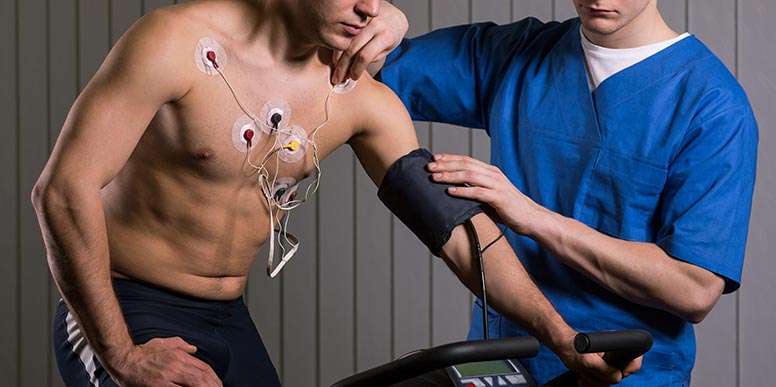

- Teste Ergométrico (Teste de Esforço)

O Teste de Esforço é mais conhecido como “Teste da Esteira” por ser realizado em uma esteira semelhante aquelas encontradas nas academias.

A principal função do teste é a de monitorar a resposta do coração diante do esforço físico.

Inicialmente são colocados eletrodos no corpo do paciente e em seguida ele deve começar a andar numa esteira.

Aos poucos a intensidade do exercício , controlada por um especialista, vai aumentando.

Entre o início e fim de cada ciclo, são registradas a pressão arterial, o ritmo e a frequência cardíaca.

O tempo de duração do teste de esforço é de cerca de oito minutos e ele pode ser interrompido caso o paciente demonstre exaustão.

Durante o teste o médico tem a possibilidade de avaliar a capacidade cardiovascular, identificar a isquemia e obter informações que auxiliarão na definição de limites seguros de intensidade de exercícios.

Se o teste na esteira não for recomendável ele pode ser feito em uma bicicleta ergométrica.